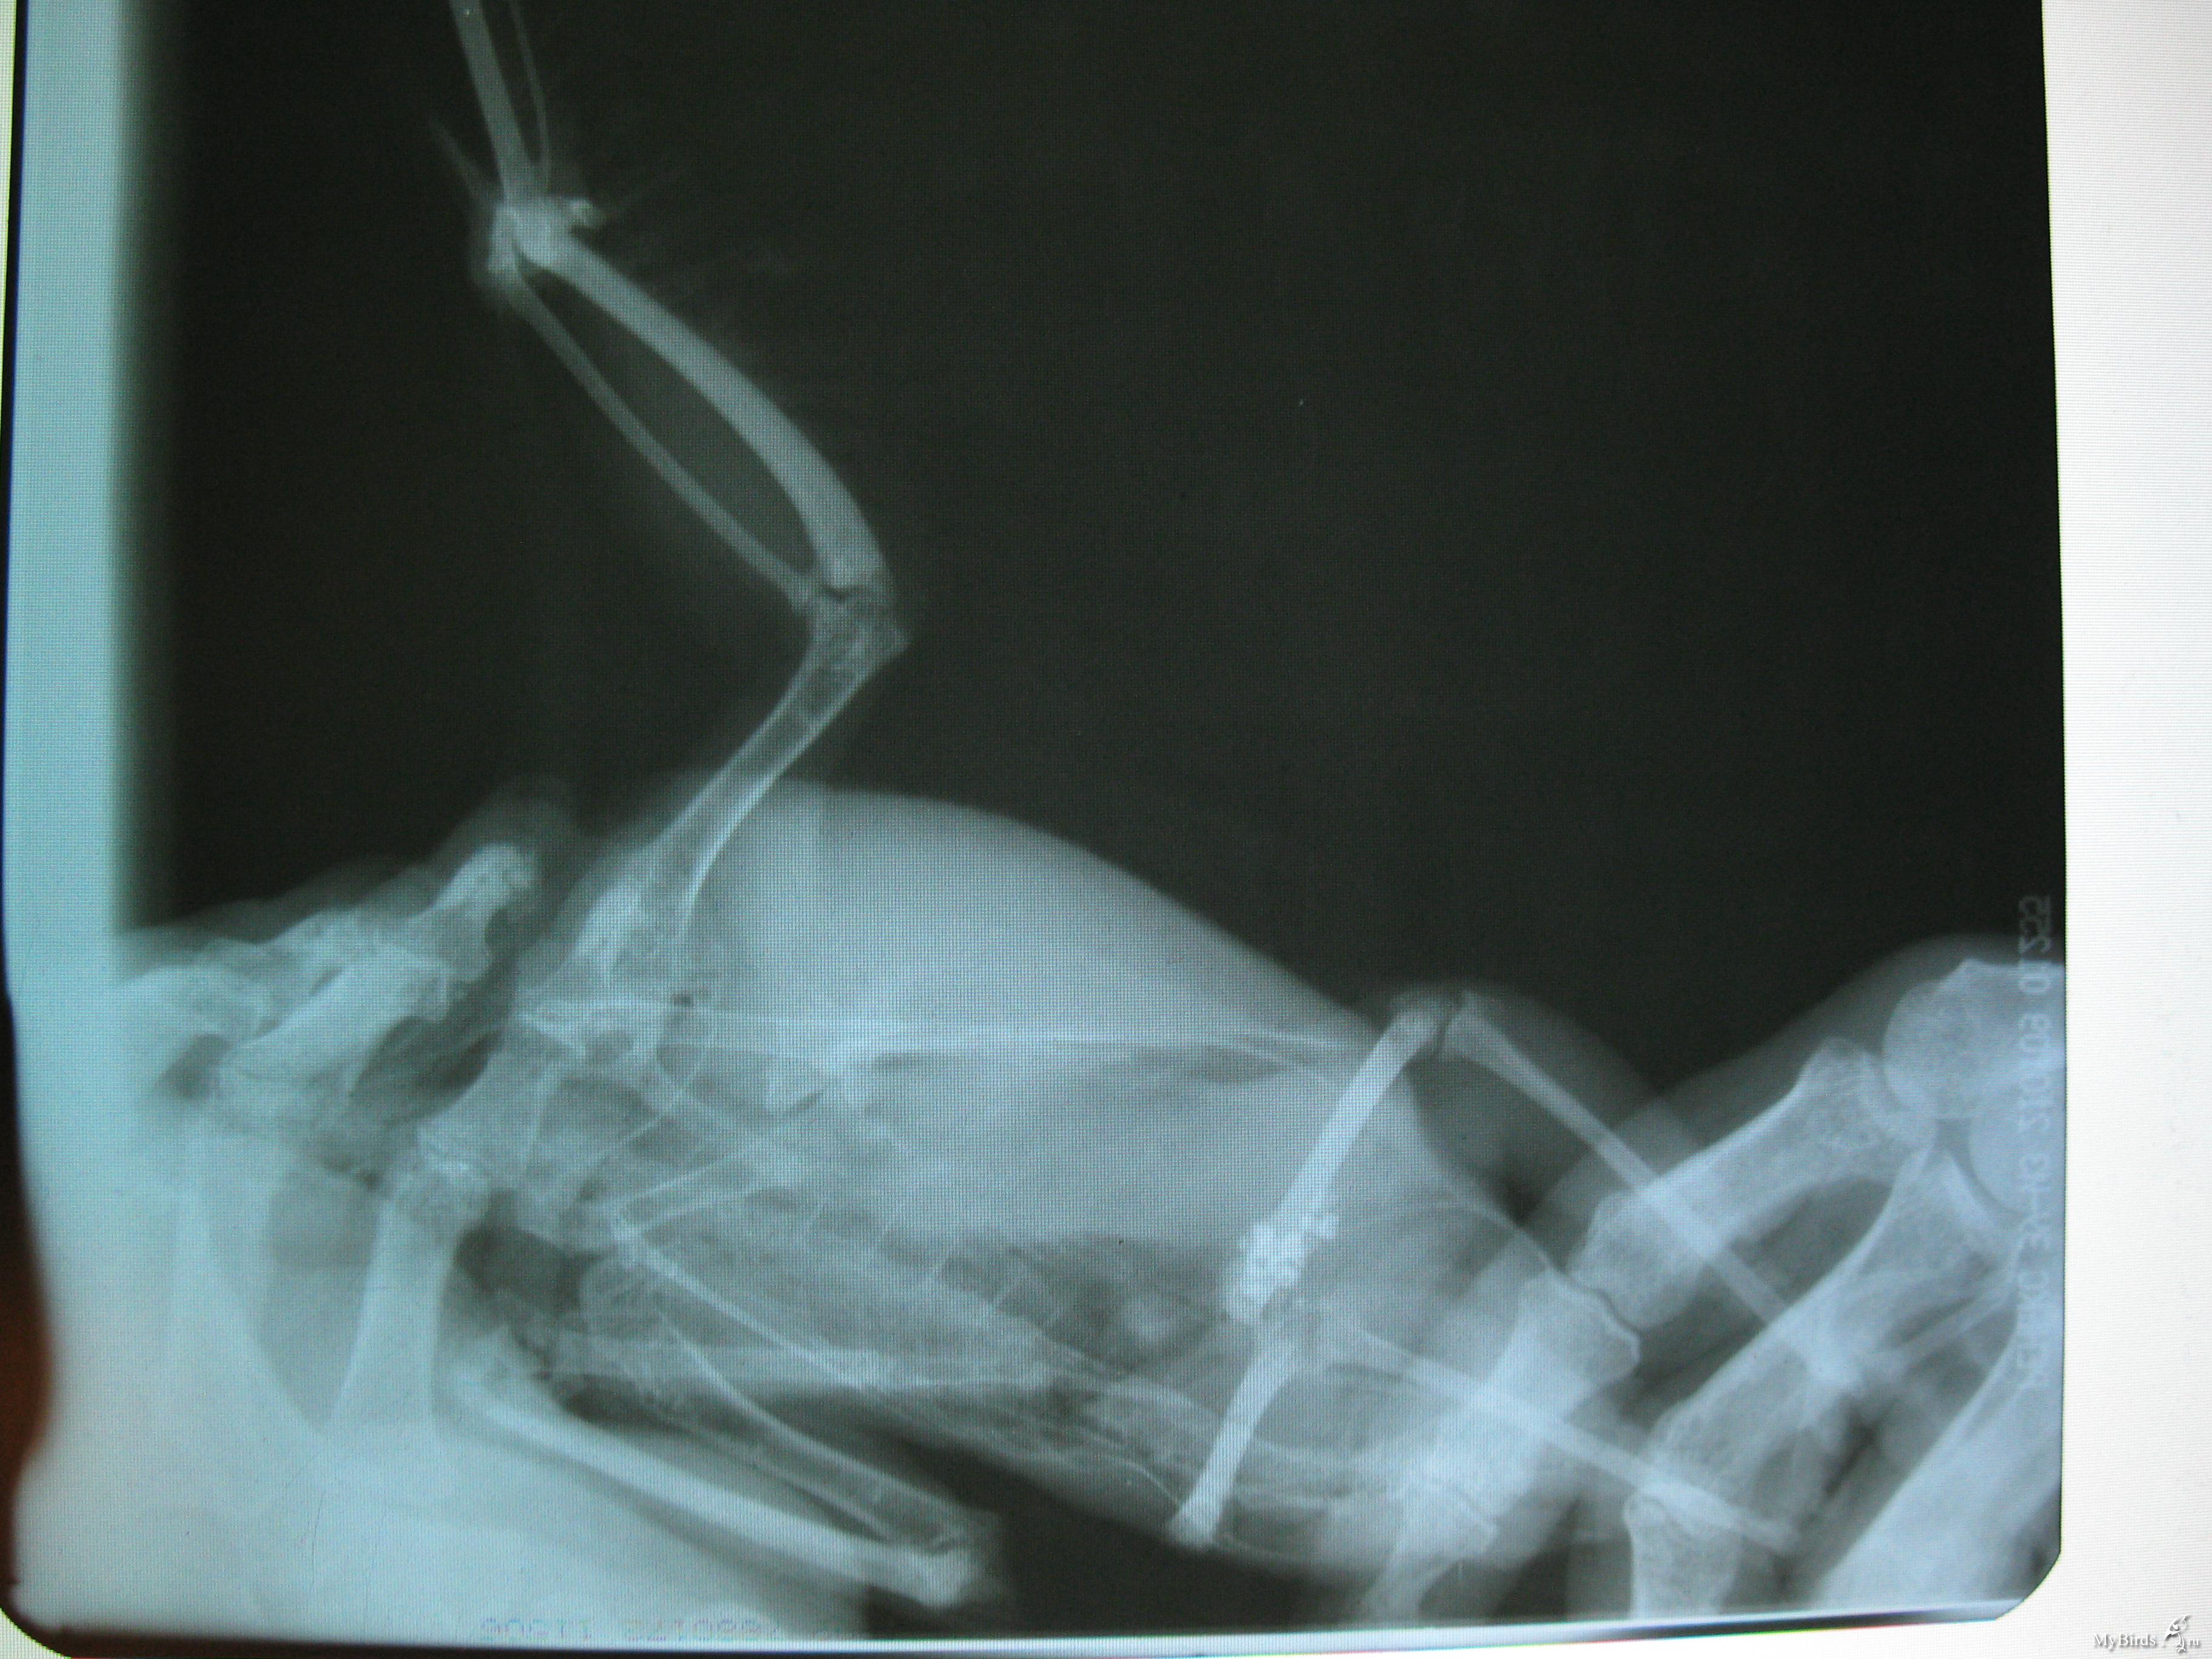

mama Ostapa Опубликовано 18 ноября, 2010 Автор #2 Опубликовано 18 ноября, 2010 на рентгенограмме я разглядела, что сломано одно из маховых перьев, как вы думаете, надо ли попросить хирурга, к которому мы поедем к 4 часам, удалить поврежденное перо?

mama Ostapa Опубликовано 18 ноября, 2010 Автор #6 Опубликовано 18 ноября, 2010 Цитата(mama Ostapa @ 17 ноября 2010, 23:28)Сделали рентгтен - переломов нет, обширная рана правого крыла. Увидеть бы.996860[/snapback] Пожалуйста, посмотрите. Что можно сказать?

mama Ostapa Опубликовано 18 ноября, 2010 Автор #8 Опубликовано 18 ноября, 2010 (изменено) Спасибо, попробую. Я прочла инструкцию от Cheshirski,Все получилось. Вот Оськино крылышко изнутри. Изменено 18 ноября, 2010 пользователем mama Ostapa

mama Ostapa Опубликовано 19 ноября, 2010 Автор #9 Опубликовано 19 ноября, 2010 Cheshirski, посмотрите. пожалуйста наши снимки. Что Вы можете сказать по этому поводу, Как и чем эффективнее лечить, чтобы нагноения не было

Cheshirski Опубликовано 20 ноября, 2010 #12 Опубликовано 20 ноября, 2010 Вы помните, сколько Оська весит? Удивительная память!997059[/snapback] Не память... Все проще - старые записи поднял. Хирург сказала, что двух уколов хватит, т.к. перорально назначен антибиотик тоже, а уколы птицы переносят плохо.997059[/snapback] Да нет, смотря что колоть. В целом - не хуже, чем человеки. Что перорально назначили? Как я поняла, это просто общеукрепляющие препараты? 997059[/snapback] Угу. Нам прописали: хлоргексидином 0,05%, затем раствором: 1 мл диоксидина 1%+10 мл физраствора 1-2 раза в день в течение 10 дней.997059[/snapback] Нормально. Но, если диоксидин переносит плохо, то можно только хлоргексидином, а после замазывать левомеколем - он потом неплохо смывается с пера.Перекись не стоит - не тот случай, это если б была опасность анаэробного воспаления... Остатки диоксидина на перьях не опасны. Пожалуйста, посмотрите. Что можно сказать?997318[/snapback] Досталось... Но, вроде, поверхностная. Вот Оськино крылышко изнутри.997343[/snapback] Хорошо. Целы косточки. Сегодня при обработке мне показалось, что раневая поверхность сухая, на месте потеряннгого пера - запекшаяся кровь.997979[/snapback] Прекрасно. Скажите, при обработке на что больше внимания уделять? Мы практически только поливаем 997979[/snapback] Достаточно, на ране только отек, воспаления не видно.